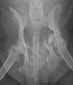

| Zugelassene

Röntgenstelle für HD

(Hüftgelenksdysplasie), ED

(Ellenbogengelenksdysplaie) und OCD

(Osteochondrosis dissecans). |